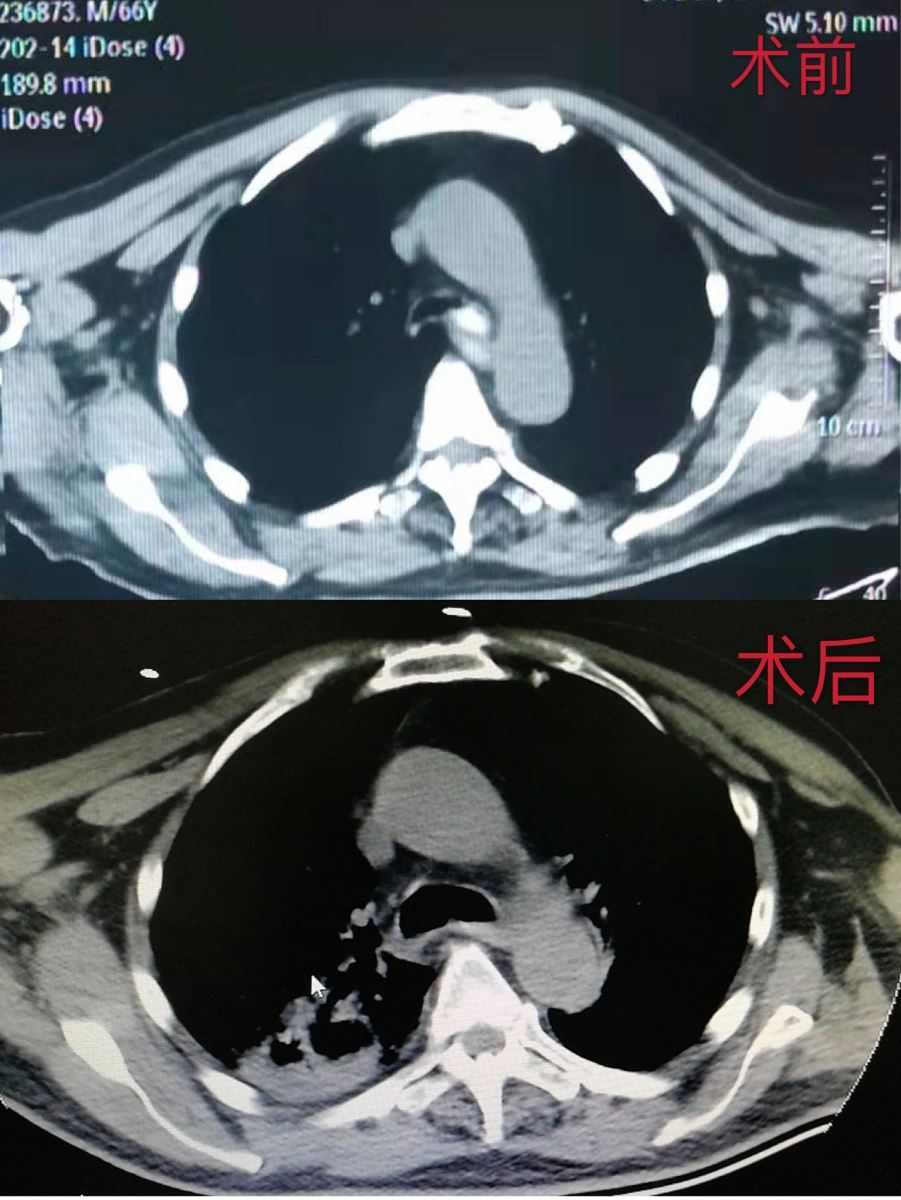

12月24日,一位常年卧床的65岁老人在吃粘豆包时不慎将残渣呛入气道,老人顿时脸色发紫,呼吸困难,胸口憋闷,家人见状立即拨打120急救电话,将老人送至就近医院进行抢救,该院为老人完善CT检查后,发现异物卡在患者左主支气管开口处,此时患者经皮血氧饱和度下降至85%(正常值为95%以上),情况十分危急,必须立即取出异物,但由于异物性质粘稠,质软且不规则,无法一次性取出,这无疑将手术难度增大,该院不具备救治能力,建议患者家属转至我院,争取最佳抢救时间。家属在得知我院是抢救老人生命的唯一希望后,立即同意转院,于11:50送入我院。来院后患者经皮血氧饱和度已下降至60%,时间就是生命,救治刻不容缓,急诊医生立即为患者进行气管插管,同时邀请呼吸内科会诊。13:02,患者被推进支气管镜室,呼吸内科张浩、何佳木医生为老人实施支气管镜下异物取出术。术中,两位医生小心翼翼地将支气管镜经口插入气管,发现异物后,立即经支气管镜的活检孔道反复深入活检钳和异物篮,到达残渣嵌顿处,将粘稠物钳住,随后稳稳地拉出呼吸道,经过反复多次努力,终于将残渣全部取出,手术结束。术后患者经皮血氧饱和度达到98%,恢复正常。至此,我院医护人员与死神的140分钟交锋宣告胜利。